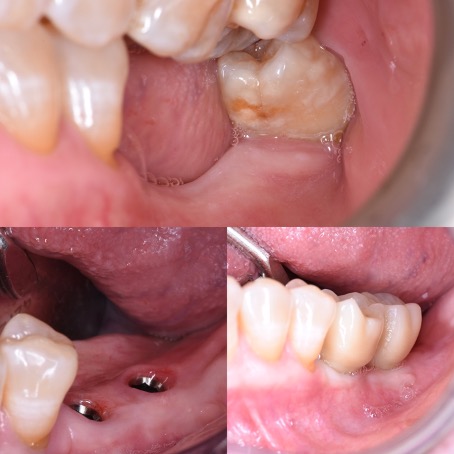

Souvent durant les premières consultations, nos patients référés nous expliquent avoir perdu l’espoir d’avoir des dents fixes à cause de la perte osseuse engendrée par l’extraction dentaire, partant du principe que l’os existant n’est plus suffisant pour accueillir avec fiabilité les implants sans connaître qu’une greffe osseuse et possible.

En effet, une reconstruction osseuse (Greffe osseuse) est indispensable, pour rétablir la hauteur ou la largeur de l’os maxillaire, avant ou en même temps que l’implantation. Ce sont soit les os du patient ou un substitut osseux qui sont utilisés comme matériau de comblement.

Les études nous montrent des résultats extraordinaires avec l’utilisation exclusive ou mélangée que ce soit avec de l’os synthétique ou de l’os autologue (os prélevé dans la bouche du patient pendant l’intervention de reconstruction osseuse).

Il y a plusieurs techniques des reconstructions osseuses et une planification correcte nous donne la possibilité de choisir la technique la plus appropriée pour chaque situation.